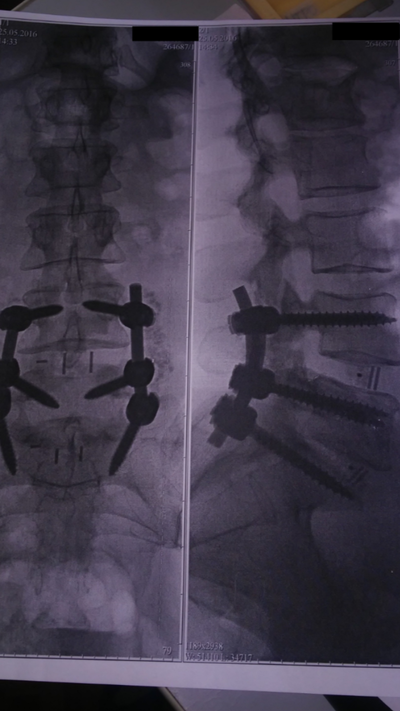

Всем привет. Хочу поделится своей историей. В 17 году у меня случилась производственная травма. Провалился пол. Летел метров 6 на арматуру. Хотя сам не строитель. Работаю АСУТП. Сломал спину-грудной отдел и две ноги. На левой пятка на пополам а правая нога раздробил стопу. Скорая увезла в больницу. Сделали две операции. В спину и в ноги поставили титановые пластины с болтами. Правую ногу ели собрали. Прошло время. А кстати дали третью рабочую группу и 40 процентов потери здоровья. На работе легкий труд. Ремонтирую и проверяю электронику. В этом году сделали снова операцию на спине. Был еще компрессионный перелом когда я получил производственную травму. Поставили кейдж систему. Это домкрат который разделяет и одновременно держит два позвонка. А что бы его установить надо старую конструкцию на спине расслабить, распороть живот. Удалить часть ребра. Так как установка ставится не со спины. И вывернуть все органы. Установить и снова зашить. Операция длилась 12 часов. В пятницу в 9 утра увезли в операционную. Но что то пошло не так. Очнулся только в субботу в 6 вечера. Врачи говорят была остановка сердца. Но я выжил. Сейчас даже незнаю что делать. Наверное дадут вторую группу. Эта история про то. Что наша жизнь такая хрупкая и не знаешь где упадешь. Случись в другом месте со мной а не в столице наверное врачи забили бы на меня. И организация помогла деньгами на операцию. Не бросила. Ниже несколько фото.